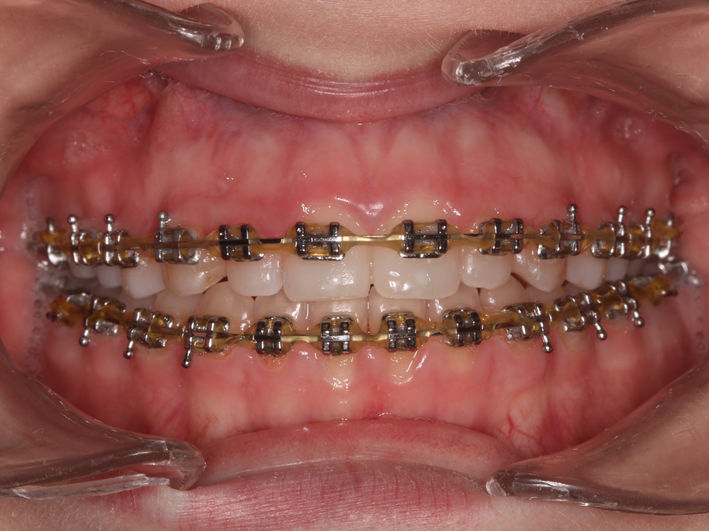

4. Tratament ortodontic pacient adult

O perioadă a existat preconcepția că tratamentul ortodontic este destinat doar copiilor sau adolescenților. Acest lucru nu este adevărat, putând fi realizat la orice vârstă. Particularitatea tratamentelor la pacienții adulți vine din prezența celorlalte patologii dentare și necesitatea colaborării cu celelalte discipline (chirurgie, parodontologie, endodonție, protetică).

În acest caz am realizat retratament endodontic 2.6, extracție 4.6, tratament ortodontic, inserare implanturi în locul dinților lipsă 1.6, 3.6, 4.6, coroane dentare din zirconiu multilayer înșurubate pe implanturi.